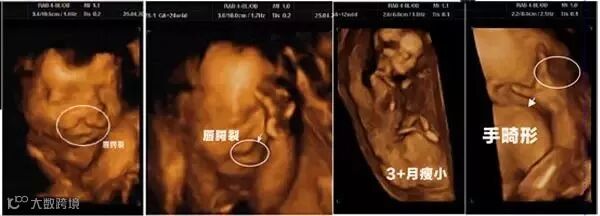

2.增加胎儿先天畸形的发生率

研究认为,可吸入的甲醛、苯系物等超标成分一旦被孕妇吸入体内,会影响胎儿的成长发育,若孕妇怀孕期间长期接触体内的激素水平也可能会受到干扰,会增加胎儿先天畸形的发生率。